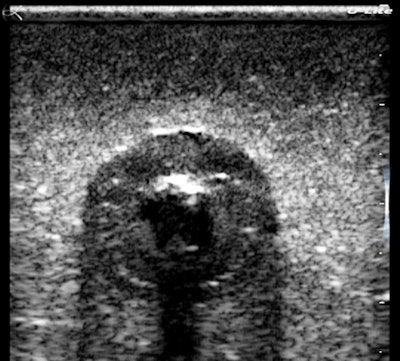

The first phantom image is of a gherkin, although I should say "cornichon," as this is a French unit. The settings were optimized for spatial resolution showing the tiny seeds along the axis.

Look at the magnified cherry images below. They hold together beautifully, and there is an impressive visible grayscale intensity range. The fluid cleft and the pitted center of the cherry have sharp clear boundaries, and there is an acoustic shadow effect deep to the cherry. These settings were mainly for contrast resolution, which is the most important performance factor for recognizing and excluding pathology. I could have done better with near-field gain and I fixed that later.